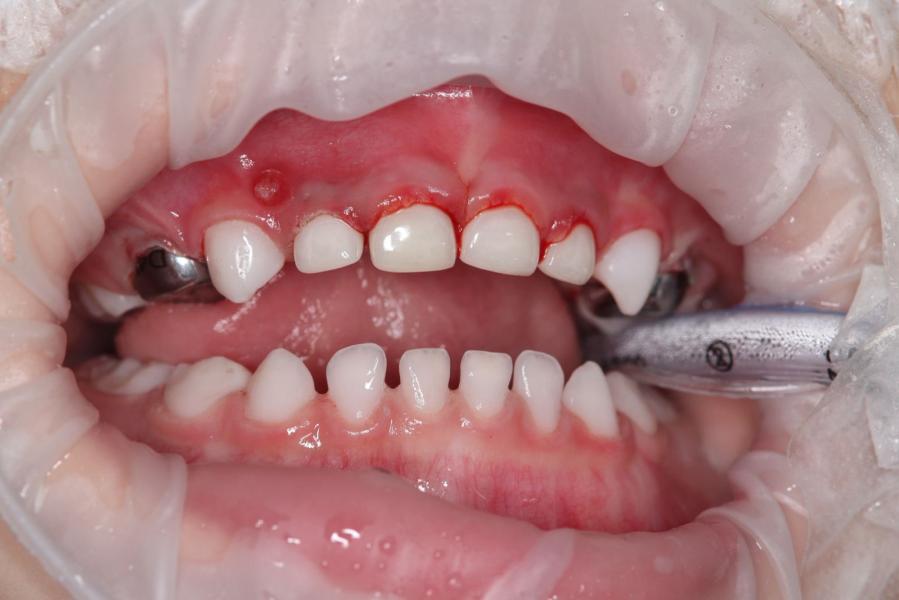

В июне сделали зубы в One dent. С третей попытки все же вылечили зубки младшему.

@_saltanat_, нижние зубы у него здоровые. Только верхние лечили. Верхний зуб один раскрошился в марте. Его наростили. На 6 Зубов сделали коронки( передние 4 и жевательные 2 верхних